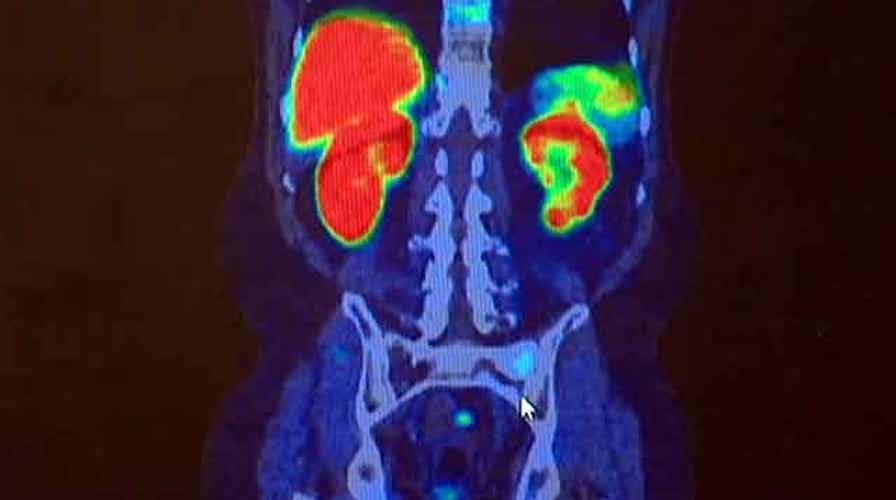

Garrett Tenney reports from Minnesota